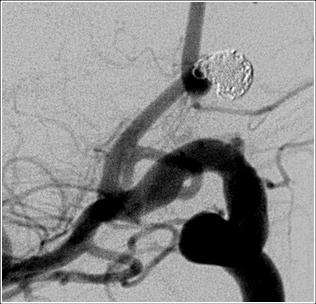

Endovascular occlusion of aneurysms includes the use of detachable coils. This is a angiographic procedure where a small soft catheter is introduced into the blood vessel from the leg artery. From there the catheter is carefully threaded up into the brain and the tip of the catheter is placed in the aneurysm (figure 6). Then through the catheter small soft coils are introduced into the aneurysm to block it completely (figure 7).

This technique of treating aneurysms with coils was invented at UCLA in 1990 and the first patient in the world was treated here in 1991. Since then, more than 1300 patients have been treated with this technique at UCLA.